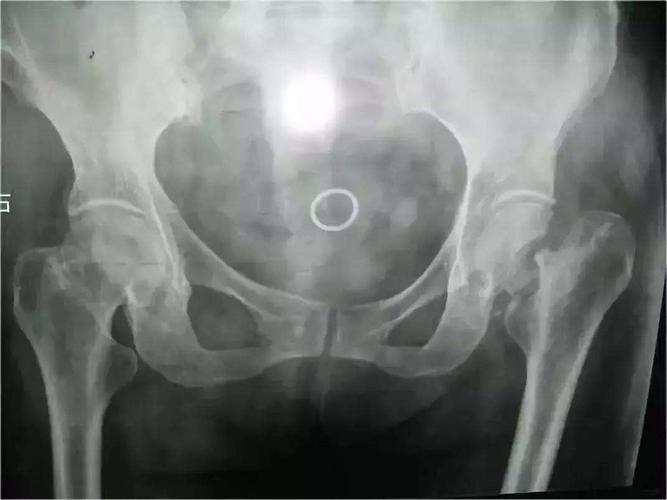

人生最后一次骨折:股骨颈骨折

医生解读:股骨颈骨折

这例股骨颈骨折怎么做好

股骨颈骨折图片

股骨颈骨折图片示意图

股骨颈骨折解剖图

股骨颈骨折的分型图片